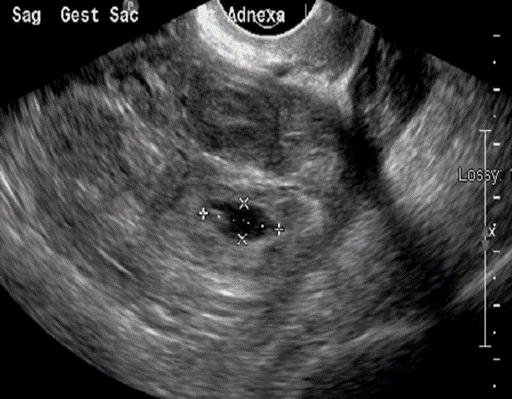

A gestational sac containing an embryo

is seen during adnexal imaging. The uterus is not visible on this image.